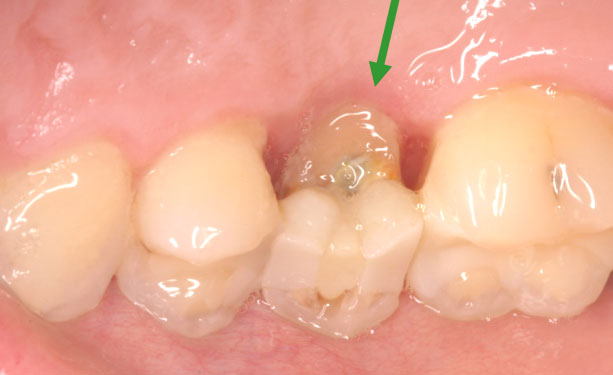

- Restorative Needs: Sometimes, a tooth may be severely decayed or fractured near the gumline, leaving little room for the placement of a dental crown. Crown lengthening helps provide the necessary space for a stable and effective restoration.

- The dentist will then make precise incisions in the gum tissue to access the tooth’s root and surrounding bone. In cases where the tooth is excessively covered by gum tissue, the dentist will carefully reshape the gumline to expose the desired amount of tooth structure. In some instances, a small portion of bone may also be removed to achieve the desired outcome.